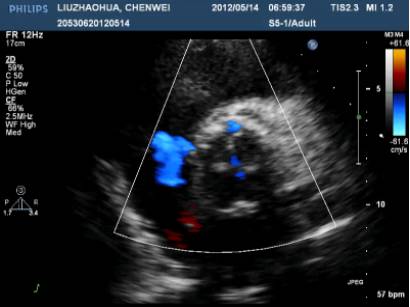

UCG示“先天性主动脉瓣发育不良,主动脉瓣二叶瓣,主动脉瓣狭窄伴轻度关闭不全,主动脉瓣赘生物形成,左心轻大,心功能正常”。

ECHO:瓣膜赘生物。

主动脉瓣二叶瓣畸形:

UCG示“主动脉瓣位生物瓣瓣架表面赘生物形成”,考虑“感染性心内膜炎”。

ECHO: